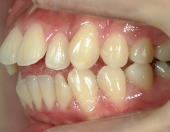

2年を少し過ぎたころには歯並びが良くなり、開咬もだいぶ改善されました。結婚式を予定していたため早期終了をさせていただきましたが、開咬が治ってハンバーガーをガブッと噛みきることができるようになって、とっても嬉しいです。式でもきれいな歯並びで、思いっきり笑うことができました。

出っ歯や八重歯などの歯並びの悪さばかりが気になっていましたが、開咬には前歯で物が噛みきれない、しゃべるときに息が漏れるなどの症状の他に、奥歯ばかりに負担がかかる為、歯の寿命を縮めてしまう可能性がありました。矯正で改善することができて本当によかっと思います。みなさんも歯並びで気になることがあったら、気軽に相談してみてくださいね。